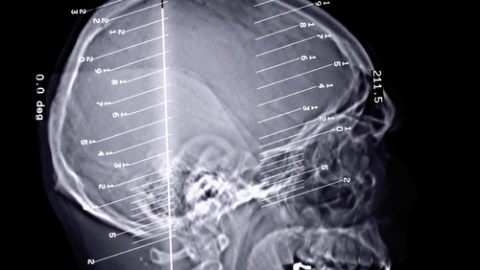

The new procedure involves an operation to insert two leads with titanium electrodes into the brain. Next, a titanium-cased battery is inserted under the skin in the chest and connected to the leads. Electrical impulses to the brain help reduce or stop epileptic seizures. Some people experience an improvement just from the insertion of the electrodes, even before they are connected to the battery.